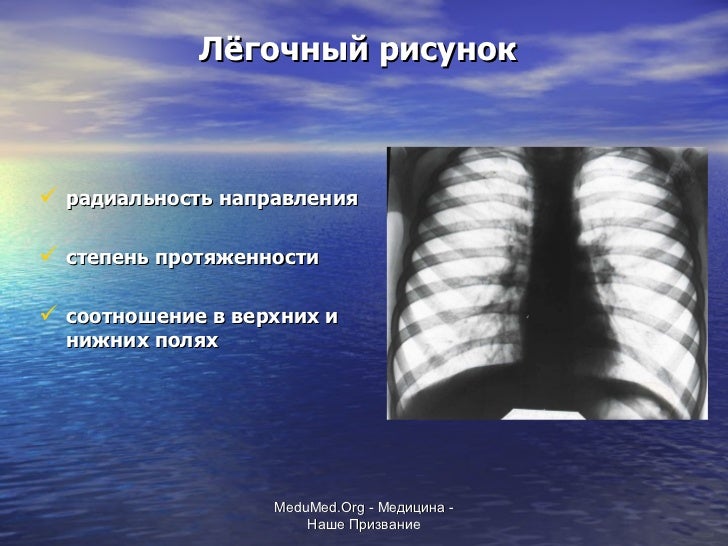

Фотографии, демонстрирующие обнаруженное усиление легочного рисунка

Раздел: Фотодневник открытий